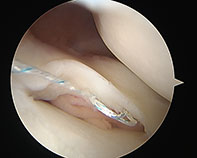

Bucket Lateral Meniscus

-

Bucket Handle Tear Meniscus

Bucket Handle Tear Medial Meniscus